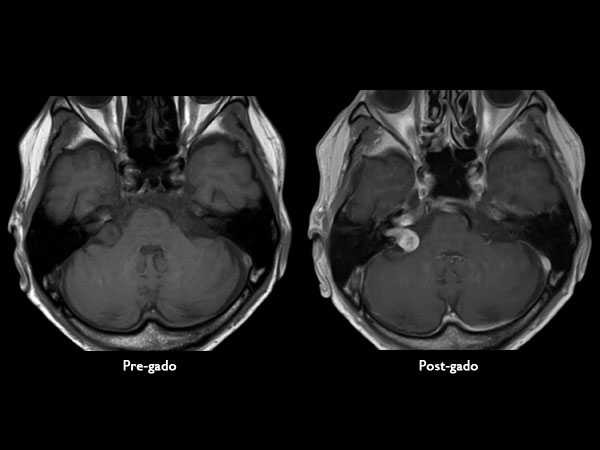

IAC – Acoustic Neuroma

Decreasing hearing of the right side. Buzzing and beating sensation in the right ear. Sometimes pain. Request for MRI of the inner ear without and with contrast agent.